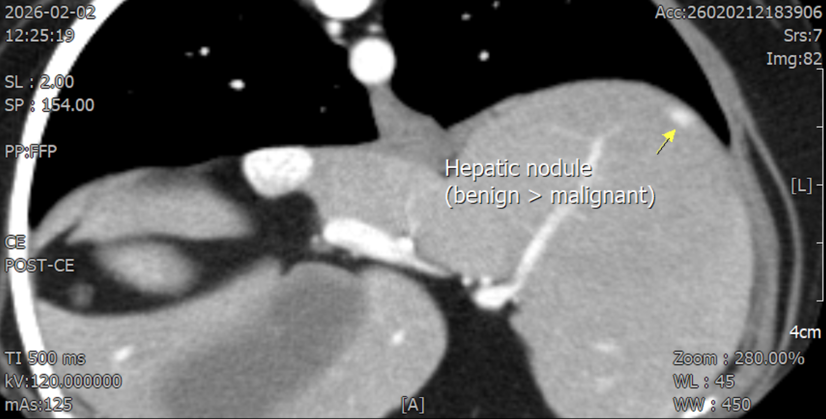

CT소견–좌측 신장 후극피질 유래의 크기 26mm*40mm의 조영 후 저감쇠성음영–간 좌측 안쪽엽에종괴가보이나 양성 병변 가능성이 더 높음–폐 우측 후엽의 미세결정 음영 CT검사상 전이 가능성은 상대적으로 낮은 상황이었습니다.